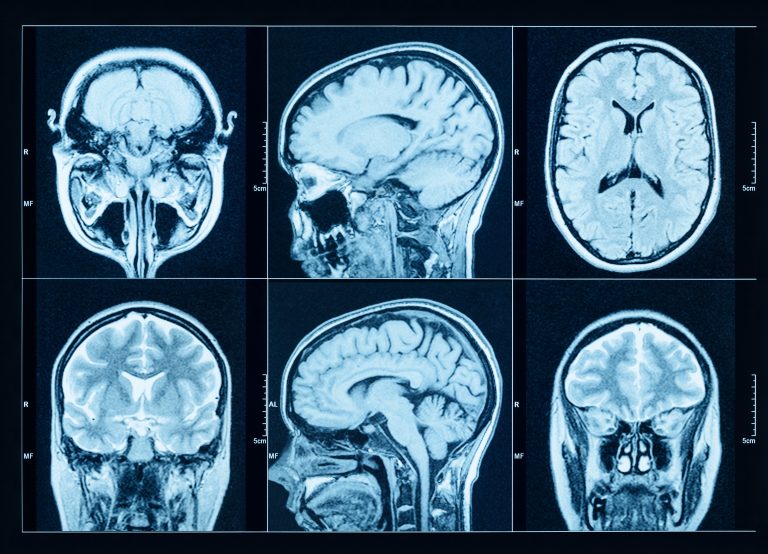

Parkinson’s disease is typically diagnosed based on clinical exam, but there are brain imaging tests that are available to help in diagnosis. This August 2025 American Parkinson Disease Association (APDA) article is all about the Dopamine Transporter Scan (DaTscan) and other brain imaging used when PD is suspected or when the clinician seeks to exclude PD.